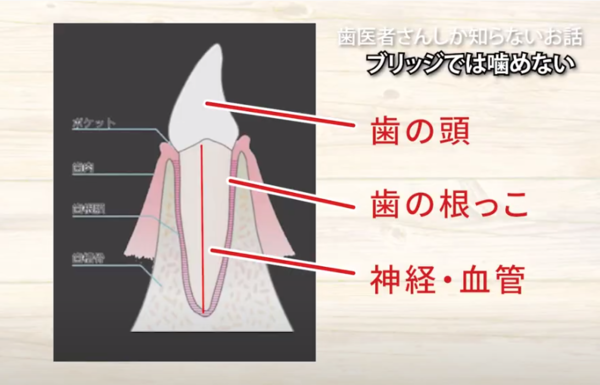

歯の頭があって

歯の根っこがあって

断面で見ますと

骨の中に

根っこが植わっていて

そこに神経、血管があるということです。

神経の治療をするにあたっては

歯の頭の部分が邪魔になるのです。

なので

歯の頭を削ってスパンと落すんです。